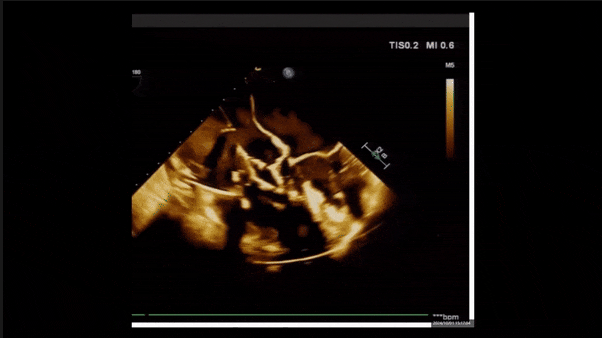

術(shù)后即刻返流

術(shù)后即刻返流三維

術(shù)后即刻經(jīng)食道超聲可見,三尖瓣假體瓣膜位置合適,牛心包瓣葉運(yùn)動狀態(tài)良好,開閉正常,瓣周及瓣葉對合緣處未見明顯返流,心電圖及心包狀態(tài)較術(shù)前無明顯變化。